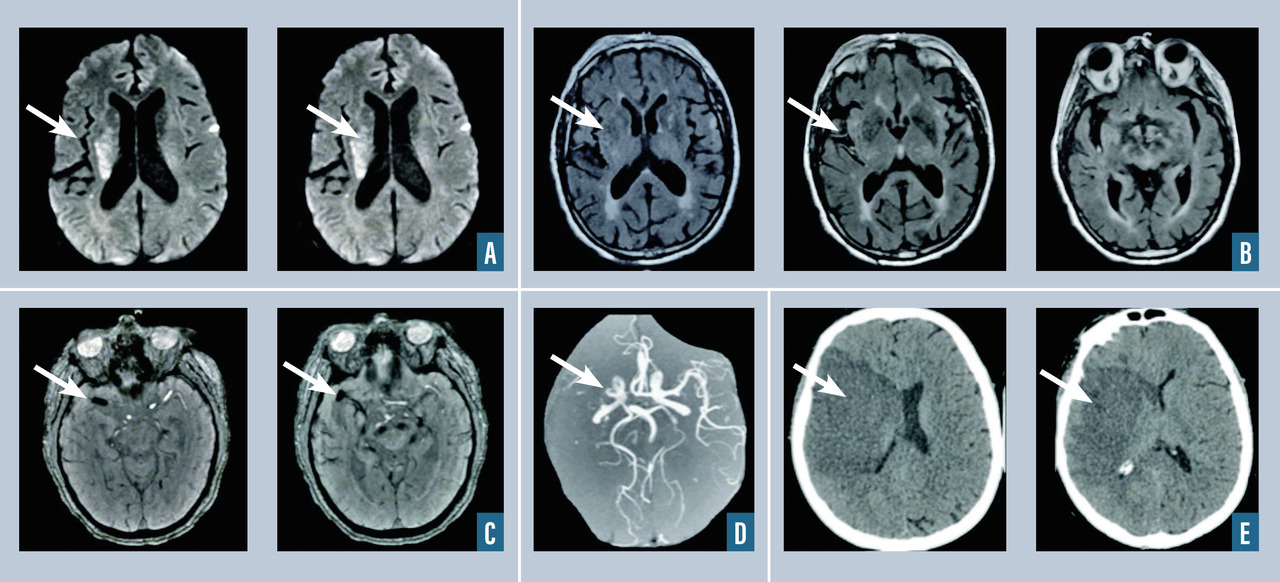

L’infarctus cérébral (fig. 1 ) correspond à un foyer circonscrit de nécrose ischémique due à l’interruption brutale de l’apport sanguin artériel par occlusion d’une artère cérébrale ou à destination cérébrale. On distingue deux types de mécanisme : l’occlusion thromboembolique (embolie du système artériel, embolie cardiaque, thrombose artérielle in situ) ou, plus rarement, des phénomènes hémodynamiques de bas débit cérébral (sur une sténose, sur un arrêt cardiaque en peropératoire). On dispose de traitement de recanalisation (chimique [thrombolyse intraveineuse] et mécanique [thrombectomie mécanique]) à fenêtre thérapeutique étroite, et d’autant plus efficace que réalisé le plus tôt possible par rapport à l’apparition des symptômes, nécessitant une prise en charge dans des filières organisées autour des unités neurovasculaires (v. Focus sur les filières de prise en charge et la thrombolyse). En effet, depuis 2004, on peut avoir recours à la fibrinolyse par rt-PA dans les infarctus cérébraux de moins de vingt-quatre heures. En 2015, les sociétes savantes neurovasculaire et de neuroradiologie ont validé le recours à la thrombectomie mécanique avec (thrombolyse combinée) ou sans (thrombectomie mécanique seule) thrombolyse intraveineuse dans les infarctus cérébraux secondaires à une occlusion proximale (carotide interne intracrânienne, artère cérébrale moyenne portion M1 et M2 proximale) dans les six heures puis dans les vingt-quatre heures suivant le début des symptômes pour certains patients sélectionnés par l’IRM de perfusion. La prise en charge des accidents vasculaires cérébraux à la phase précoce a fait l’objet de recommandations de la HAS en 2009 et les sociétés savantes (SFNV, ESO) mettent régulièrement à jour les recommandations sur la prise en charge de l'AVC à la phase aiguë et en prévention secondaire. L’IRM cérébrale avec séquences de diffusion, FLAIR, T2* et ARM-TOF est l’examen de référence pour le diagnostic d’infarctus cérébral récent (hypersignal en diffusion, qui devient visible après 4 à 6 heures en FLAIR), d’occlusion artérielle (ARM-TOF). Elle permet également d’éliminer une hémorragie (T2*). Le recours à l’IRM de perfusion permet de sélectionner, via un logiciel de lecture automatisé, les patients pouvant bénéficier d’une thrombectomie mécanique entre six et vingt-quatre heures après le début des symptômes. Les causes des infarctus cérébraux sont dans 30 % des cas athérothrombotiques, dans 20 % cardio-emboliques (fibrillation atriale), dans 20 % d’origine lacunaire dans le cadre d’une maladie des petites artères. Dans 25 % des cas, la cause reste indéterminée à l’issue du bilan.

L’hématome intracérébral est une collection de sang consécutive à la rupture d’un vaisseau intracrânien (fig. 2 ). L’hypertension artérielle est la première cause, et l’hémorragie est alors très souvent localisée au niveau des noyaux gris centraux. Lorsque l’hémorragie est située en superficie, elle est dite lobaire, et après 50 ans, le diagnostic d’angiopathie amyloïde est fréquemment rencontré après exclusion des autres diagnostics (tumeurs, traumatisme…). Une autre cause est la rupture d’une malformation vasculaire, que ce soit une malformation artérioveineuse, un anévrisme ou un cavernome. Parmi les autres causes, on cite la thrombophlébite cérébrale et les troubles de la coagulation spontanés ou iatrogènes (traitements antithrombotiques). Le scanner cérébral, qui est l’examen de référence en cas d’hémorragie cérébrale, met en évidence une plage en hyperdensité et est le plus souvent complété par un scanner cérébral avec injection et un angioscanner cérébral à visée étiologique (recherche de tumeur, de malformation vasculaire, de thrombose veineuse cérébrale). L’IRM cérébrale avec ARM peut être intéressante lorsque le scanner n’est pas contributif pour rechercher une cause de l’hémorragie (stigmates de maladies des petites artères liées à l'âge et à l'hypertension artérielle, angiopathie amyloïde, tumeur cérébrale). En l’absence de cause retrouvée à la phase aiguë, l’IRM cérébrale injectée doit être réitérée à trois mois pour s’assurer de l’absence de lésion sous-jacente. Le recours à l’artériographie cérébrale est fréquent dans le cadre du bilan étiologique de l’hématome du sujet jeune, en l’absence de cause évidente.

La thrombose veineuse cérébrale correspond à l’occlusion d’un ou de plusieurs sinus veineux cérébraux et/ou des veines corticales (fig. 3 ). On distingue la thrombose veineuse cérébrale sans lésion parenchymateuse, responsable d’un tableau d’hypertension intracrânienne, et la thrombose veineuse cérébrale avec œdème cérébral (« infarctus veineux ») ou avec hématome cérébral, responsable d’une présentation clinique souvent bruyante pouvant associer des convulsions, un déficit neurologique focal, voire un coma. L’imagerie cérébrale met en évidence des signes directs de thrombose sous la forme d’une hyperdensité spontanée du sinus ou de la veine sur le scanner cérébral sans injection (signe du sinus spontanément hyperdense ou de la corde dense) ou en montrant sur l’IRM un hypersignal en T1 et en T2 du sinus thrombosé. Les séquences injectées veineuses (en IRM ou en angioscanner) montrent l’absence d’opacification ou l’opacification partielle du sinus occlus du fait de la présence du thrombus. L’IRM cérébrale avec séquences veineuses (VRM) et l’angioscanner veineux ont actuellement une sensibilité et une spécificité relativement proches pour le diagnostic de thrombose veineuse cérébrale. Les signes indirects de thrombose veineuse cérébrale sont la présence d’un « infarctus veineux » ou d’une hémorragie cérébrale ou méningée sulcale, qui sont des conséquences possibles de la thrombose veineuse cérébrale.